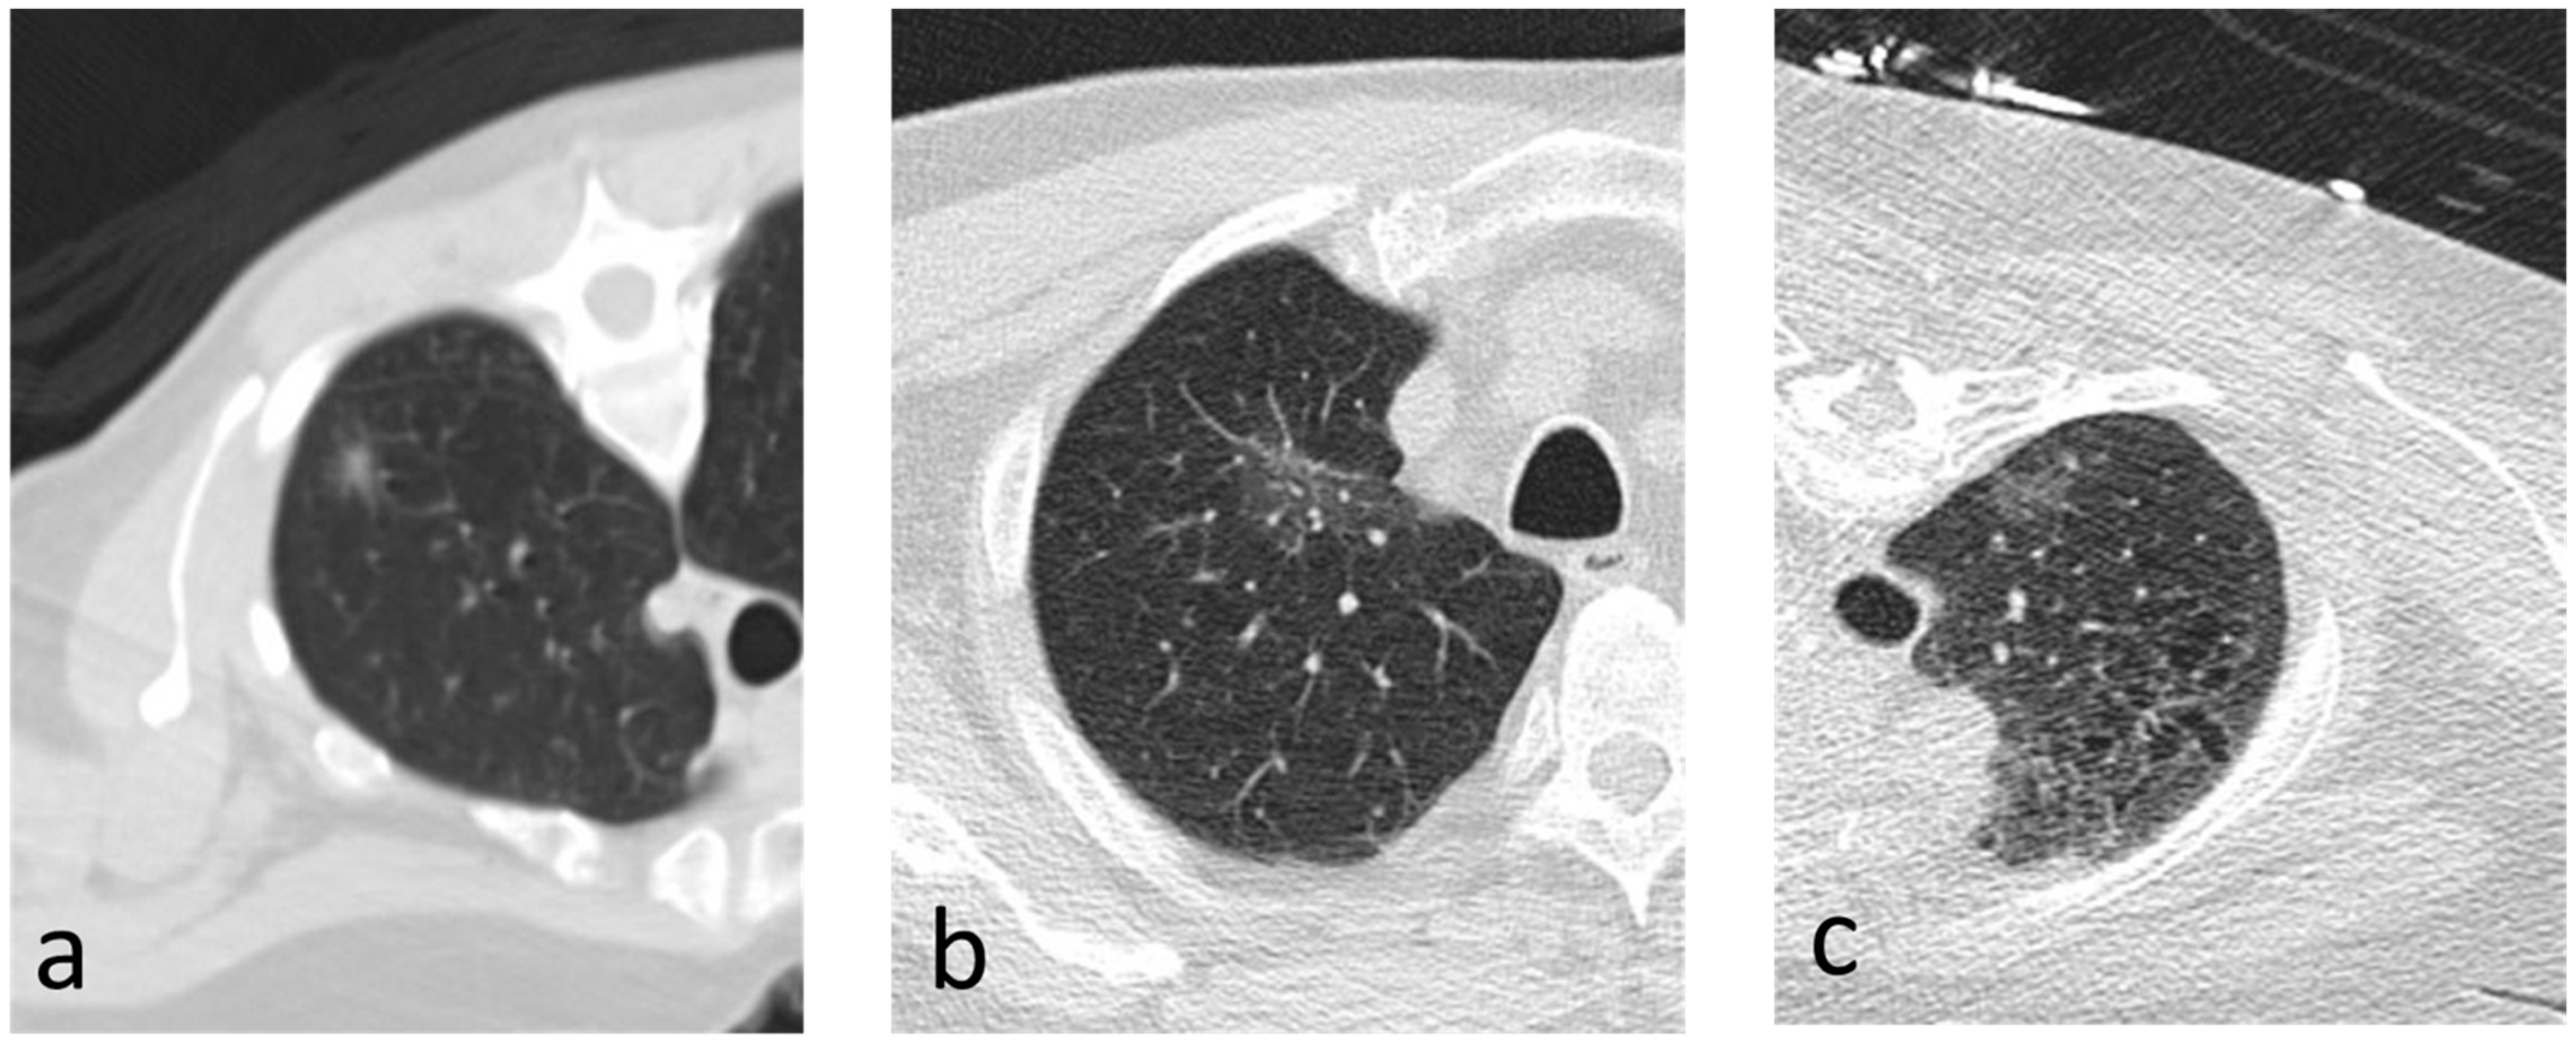

Figure 3.

(a–c) Axial images depicting nodules that were found to be invasive on resection.